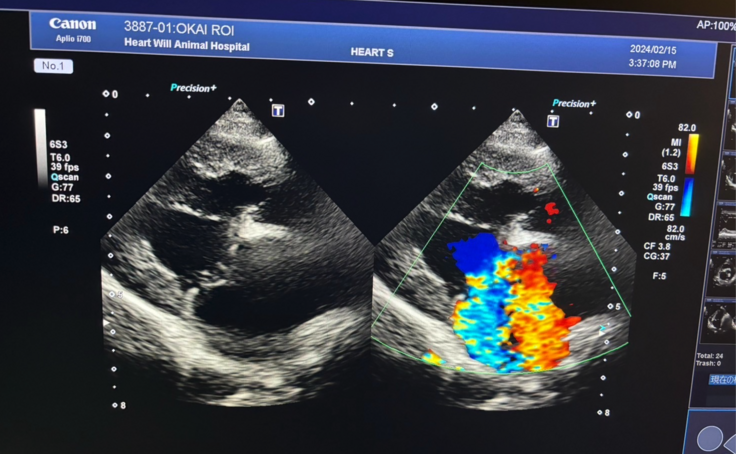

▽エコー写真

△ 左の画像 : 心臓の弁が閉じてなく、右の画像 : 色ついてるが漏れ出している血液です。逆流の量は多め。